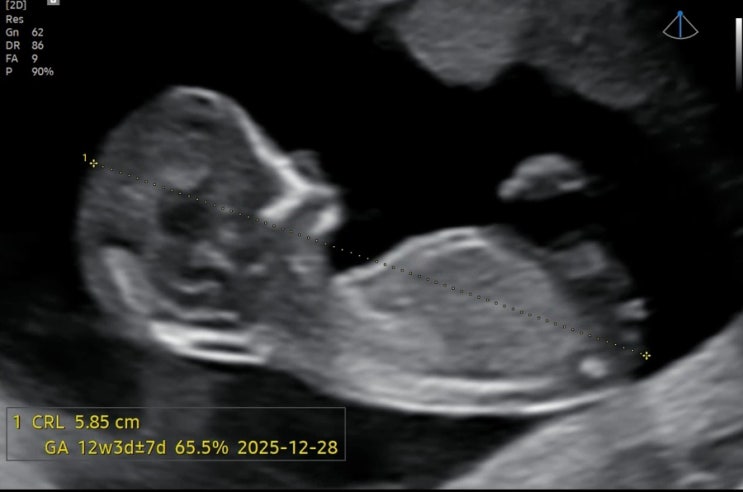

[임신일기 12주] 1차 기형아검사(목투명대,코뼈 확인)/B형간염 항체 없음/장꾸맘 각도법/초음파 각도법/중국황실달력/태몽 성별 예측

12주0일 1차 기형아 검사와 입체 초음파를 보는 날 초코우유를 먹으면 아기가 잘 움직인다길래 한 통 싸악 ...